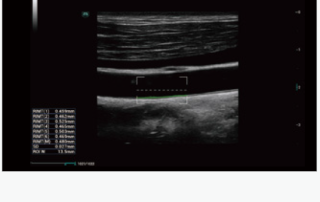

Mindray Ultrasound Consona N9